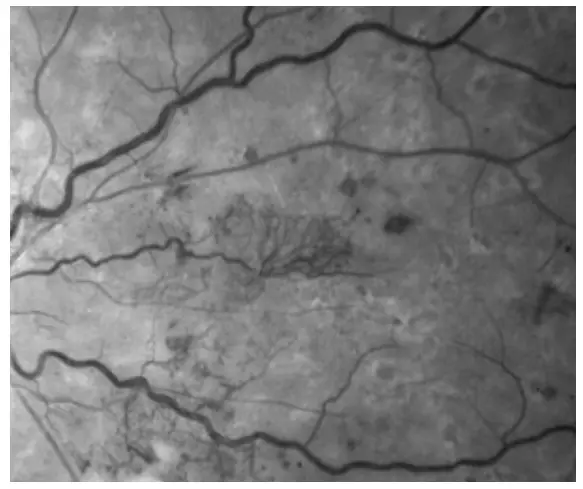

RGB Channel Separation

True Color images can be separated into red, green and blue channel images, which can enhance the visual contrast of details in certain layers of the retina. Red channel images reveal the choroid in more detail. This may be helpful in visualizing choroidal lesions such as nevi or tumors. Green channel images provide excellent contrast of the retina, especially of vasculature and hemorrhages. Blue channel images increase visibility of the anterior retinal layers, allowing easier visualization of retinal nerve fiber layer (RNFL) defects and epiretinal membranes.

- Green channel image of diabetic retinopathy.